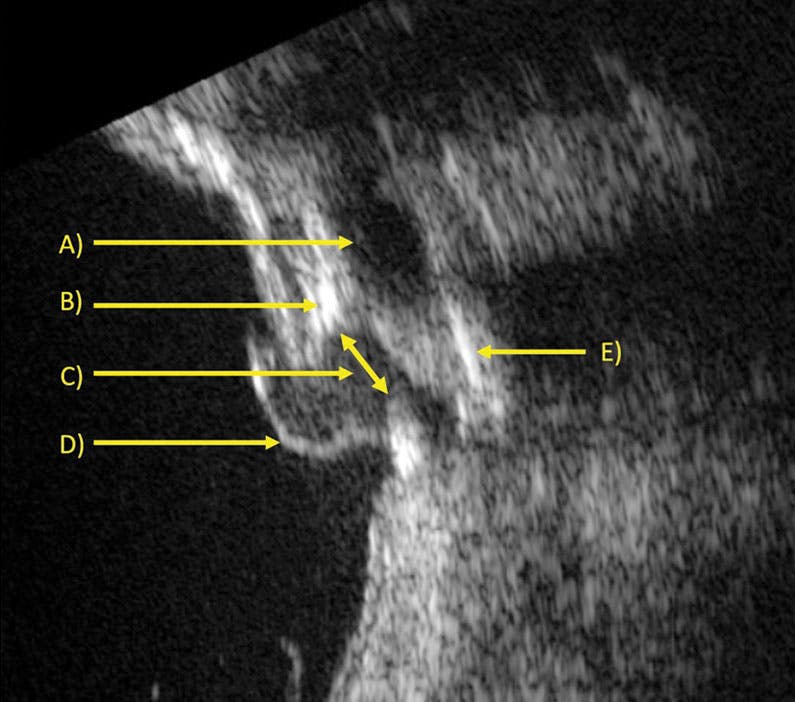

The interpretation of ocular ultrasound is not always straightforward and requires clinical context. In our patient, the complex surgical history of scleral flaps and MIRAgel buckle implantation aided in our analysis. The B-scan revealed residual MIRAgel material, as hydrogels are hydrophilic and absorb water and thus are hypoechoic on ultrasound (Figure 2A). There are several areas of likely calcified sclera or MIRAgel material (Figure 2B and E), as these buckles are known to calcify over time.10,11 Ultrasound also showed a full-thickness break in the sclera with an absent choroid (Figure 2C) and a detached retina (Figure 2D). Interestingly, the retina protruded outward rather than toward the scleral rupture, likely due to stabilized extraocular pressure and IOP.

<p>Figure 2. B-scan ultrasound demonstrates likely residual MIRAgel implant (A), probable calcification of the sclera or buckle (B), a scleral rupture (C), a detached retina (D), and probable calcification of the scleral flap or buckle (E).</p>

Figure 2. B-scan ultrasound demonstrates likely residual MIRAgel implant (A), probable calcification of the sclera or buckle (B), a scleral rupture (C), a detached retina (D), and probable calcification of the scleral flap or buckle (E).